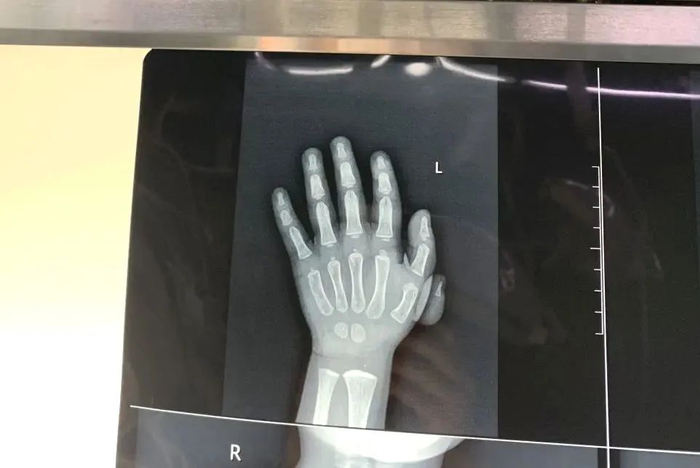

来自云南的小尹因为手指先天畸形,上幼儿园时经常被嘲笑。“她回来后就很难过,有一次拿起剪刀想剪掉它。”小尹的奶奶说。日前,杨浦区中心医院专家团队远赴云南省丽江市永胜县人民医院,为小尹开展矫形手术,手术很成功。此次杨浦区中心医院专家团队共为3名学龄前多指患儿完成矫正手术。

这是由上海援滇医疗队发起的“先天多指畸形”爱心公益项目。“我们不仅要带给他们健全的身体,更重要的是给孩子们送去精神上的陪伴和情感上的关心。”上海驻昆办副主任柳春杰表示。

杨浦援滇干部顾益军介绍,该项目由永胜县卫健局牵头,依托永胜县人民医院骨科和麻醉科共同完成,并分阶段实施。

近年来,在沪滇合作的大力支持下,杨浦区卫健委派出援滇医疗队对口支援永胜县人民医院。去年11月,杨中心医院援滇医疗队在永胜县下乡义诊时,发现了两名拇指多指畸形患儿,与家长沟通后,得知其家境贫困,难以到昆明、大理等地的医院就医。于是,医疗队在当地为这两名患儿进行了矫形手术。

基于这次经历,杨中心援滇医疗队推测永胜县其他乡镇可能存在类似情况,便向永胜县政府建议对各乡镇进行多指畸形筛查。“当地不少患有先天性疾病的孩子,因其家庭居住在偏远山区交通不便、医疗条件有限、经济困难等原因,未能得到及时诊治。”杨中心援滇医疗队队员李波说。

“今年5月,永胜县开始在全县开展初步筛查,共筛查出46例多指畸形。我们将为这些患者评估其畸形严重情况,并制定合适的手术方案,免费为其进行矫形手术。”顾益军表示,首批为学龄前儿童和成人的多指畸形开展矫形手术,接下来,将在暑期完成学龄儿童的矫形手术。术后还将开展定期随访,指导患者进行康复功能锻炼。